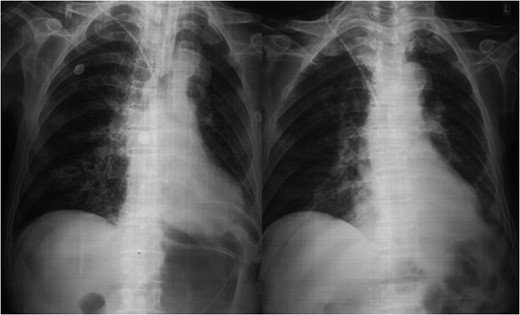

An 80-year-old man presented to our emergency room with multiple episodes of non-bilious vomiting for 4 days and not-passing stool or flatus for 2 days. He also complained of intermittent pain in the upper abdomen, which was not associated with fever, chest pain, melena or diarrhea in the recent past. However, he complained of increased cough and shortness of breath for the last 4 days on the background of a diagnosed chronic obstructive pulmonary disease. There were no similar complaints in the past. On examination, his vital parameters were normal, other than an oxygen saturation of 82% for which oxygen had to be given via face mask. His abdominal examination revealed epigastric fullness with tenderness in the epigastric and right hypochondrium. There was no evidence of peritonitis. Laboratory investigations revealed hypokalemia (3.1 mEq/l) with other parameters being normal. On the chest X-ray obtained, we saw air–fluid levels in the right thoracic cavity (Fig. 1). Computed tomography (CT) scan of the abdomen performed demonstrated a right anterior diaphragmatic hernia with stomach as content. (Figs 2 and 3) The patient was taken to the operating room, and an upper midline laparotomy was performed. Findings included an ~4 × 3 cm defect to the right of the sternum in the anterior diaphragm (Fig. 4), with incarcerated pylorus/antrum of stomach as contents and a grossly distended stomach. Rest of the bowel was normal. The contents were reduced, and the defect closed primarily with 2-0 non-absorbable interrupted mattress sutures (Fig. 5). Postoperative period was uneventful, and chest X-ray revealed a corrected defect with reduced contents (Fig. 6). The patient was started orally on the first postoperative day and discharged on the sixth postoperative day.

Diagnosis is usually suggested by chest X-rays indicating an air–fluid level in the chest with Barium studies revealing contrast in the stomach/bowel herniating through the diaphragm. CT scan of the chest and diaphragm are highly accurate and help proceed with surgical management [7].